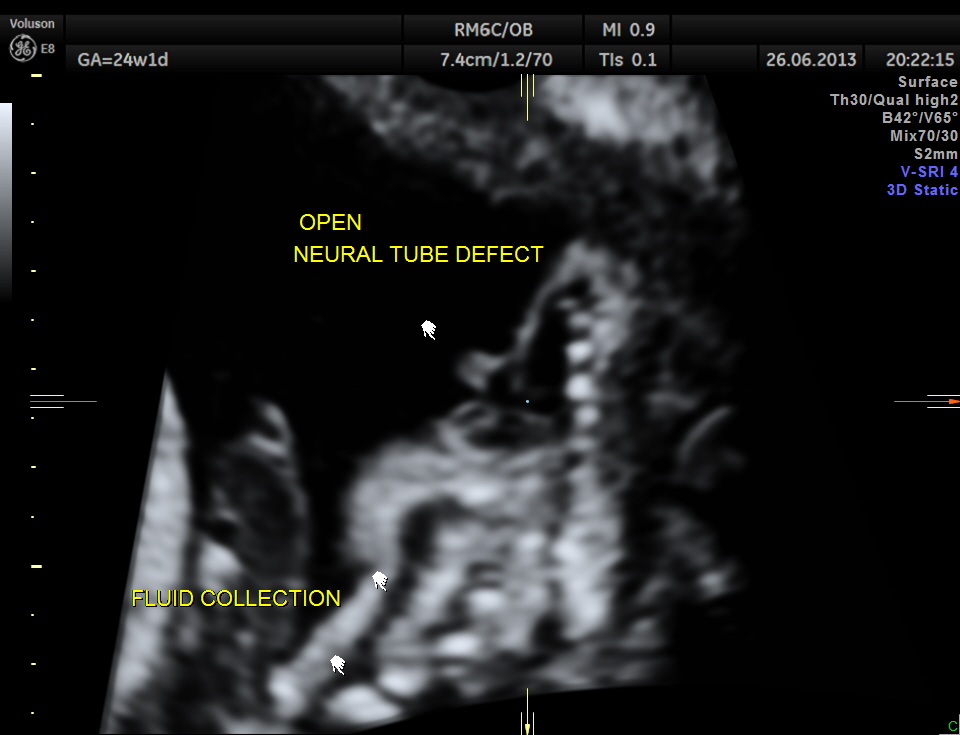

the following image shows the open neural tube defect at the same level as the heart.